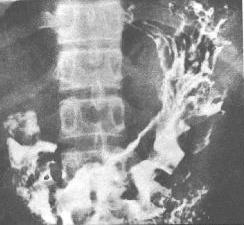

病理改變

病變可為瀰漫性,或僅限於胃竇部黏膜的卡他性炎症。黏膜充血水腫,表面有滲出物及粘液覆蓋,可有點狀出血和不同程度的糜爛。

因有膜有淋巴細胞、中性粒細胞、漿細胞及少數嗜酸粒細胞浸潤、水腫、黏膜血管充血,偶有小的間質性出血,嚴重者黏膜下層水腫、充血。